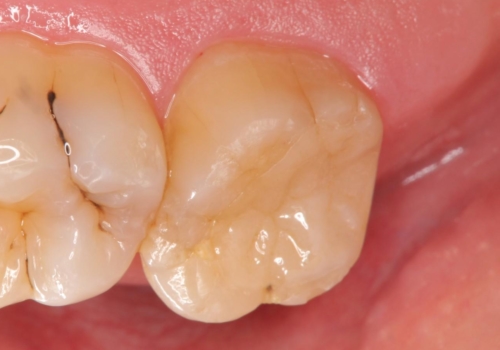

銀歯の劣化・セラミックインレー修復

銀歯辺縁からのセメント漏洩が認められたため、セラミックインレーによる精度の高い修復を行うこととなりました。

劣化の速度が遅い材料を用いて、精度の高い修復を行うことで長期的な予後が期待できます。